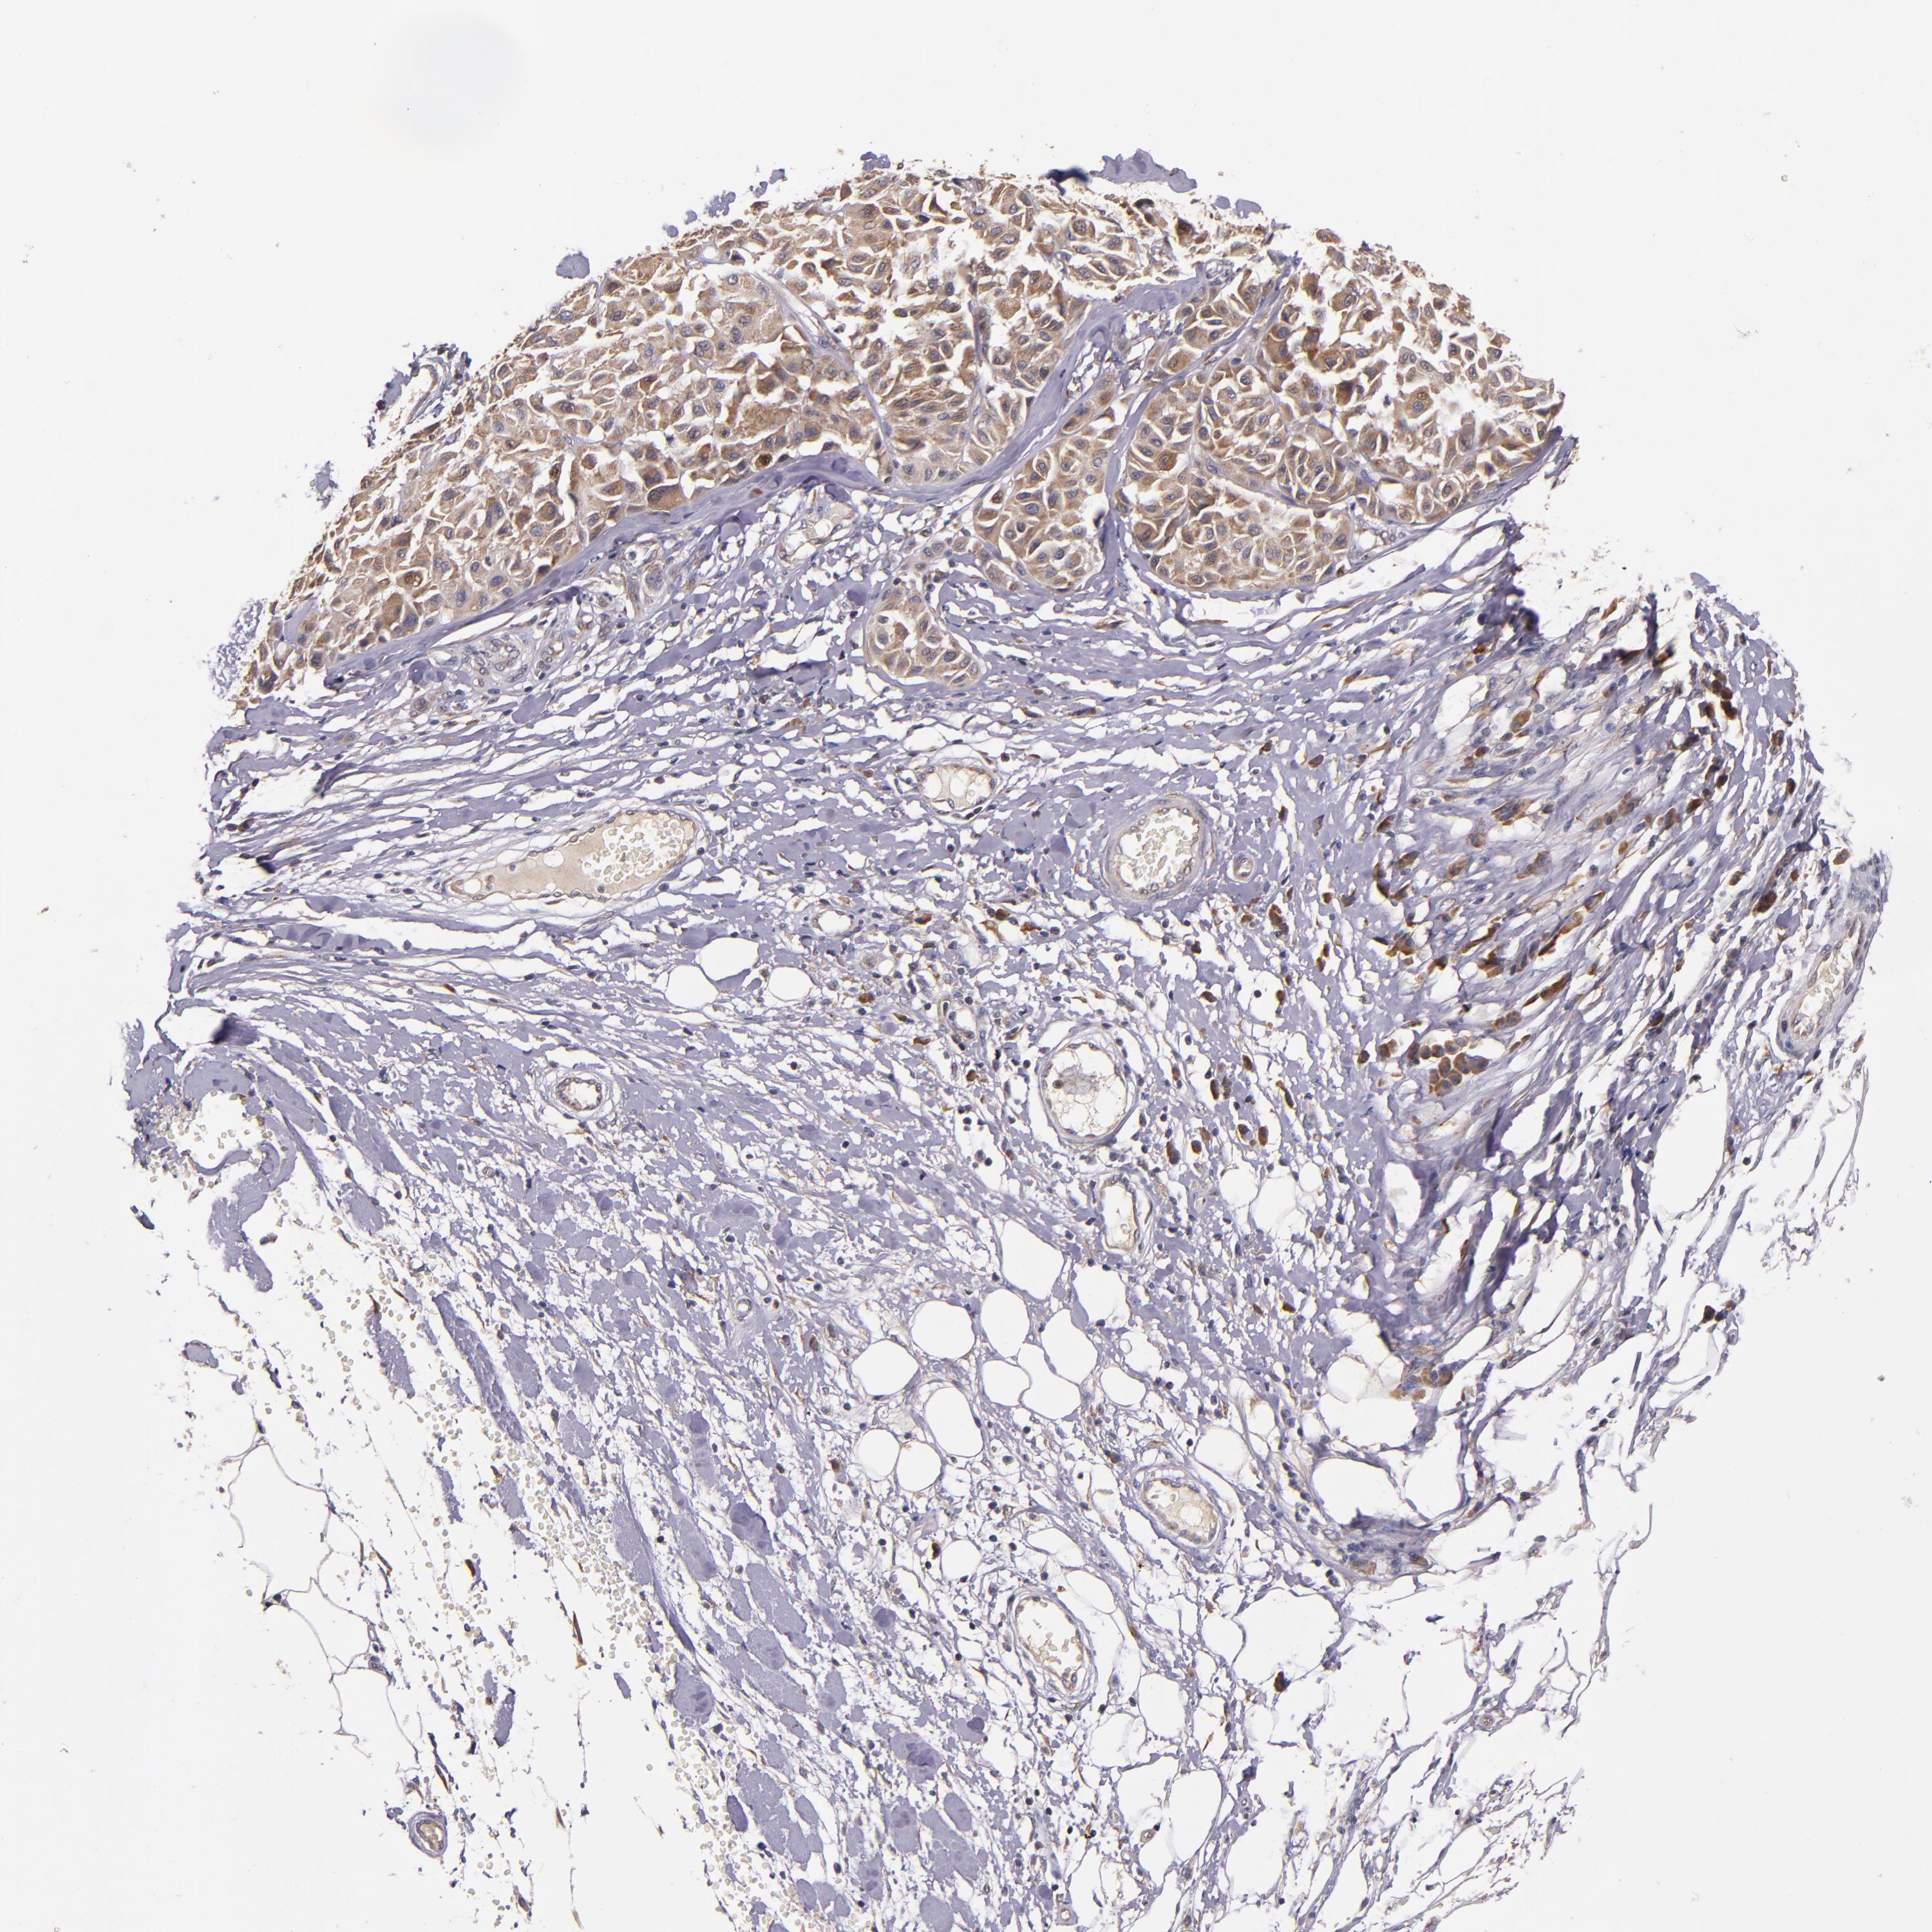

MELANOMA - Protein expressioni

A mouse-over function shows sample information and annotation data. Click on an image to view it in a full screen mode. Samples can be filtered based on level of antibody staining by selecting one or several of the following categories: high, medium, low and not detected. The assay and annotation is described here.

Note that samples used for immunohistochemistry by the Human Protein Atlas do not correspond to samples in the TCGA dataset.

Antibody stainingi

Antibody staining in the annotated cell types in the current human tissue is reported as not detected, low, medium, or high, based on conventional immunohistochemistry profiling in selected tissues. This score is based on the combination of the staining intensity and fraction of stained cells.

Each image is clickable and will lead to virtual microscopy that enables deeper exploration of all samples and also displays staining intensity scores, fraction scores and subcellular localization as well as patient and tissue information for each sample.

Antibody HPA002859

Antibody CAB011655

Staining

High

Medium

Low

Not detected

Intensity

Strong

Moderate

Weak

Negative

Quantity

>75%

75%-25%

<25%

None

Location

Nuclear

Cytoplasmic/membranous

Cytoplasmic/membranous,nuclear

Malignant melanoma, NOS

Malignant melanoma, Metastatic site